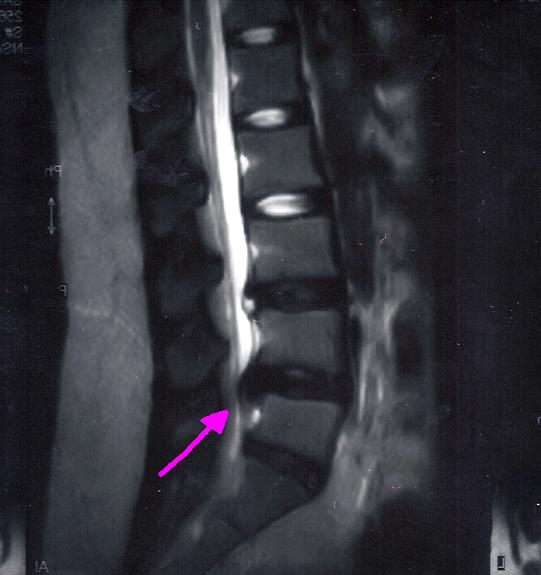

今日2ヶ月半ぶりのMRIを撮ってきた。

よくなってなかった。

むしろ、悪い方向に・・・

飛び出したヤツが、白くなっている=固まっていきよる

って言われた・・・・